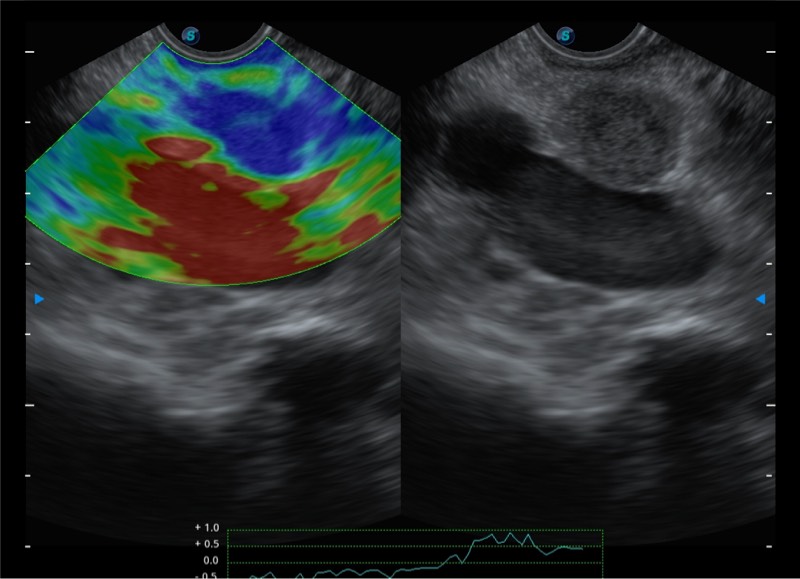

搭载百万级CMOS成像技术

及自主研发凸阵换能器,

可呈现优质的内镜和超声画面

基于二十年的超声技术积累,竞技宝(JJB)官方网站提供了最新一代的独立超声主机,在提供高质量图像的同时满足多学科使用。具备常见多普勒技术并提供弹性成像、声学造影等高端影像技术。新一代传感器具有更强的抗干扰能力并减少图像伪影。

4-12MHZ宽频输出